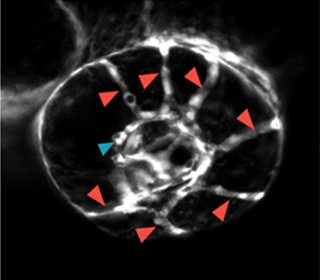

この遺伝子は新規であるため機能情報が無く、本当に血管の形成にかかわる遺伝子であるかどうか分かりませんでした。そこで、ゼブラフィッシュでこの遺伝子の発現を抑制してみることにしました。発達期にこの遺伝子の発現を抑制すると、頭蓋内の眼動脈や脊椎動脈の分岐の異常が出ることが分かりました。特に、頭蓋内の眼動脈の分枝異常は過去に報告されたことのない非常に興味深いものでした(図1)。血管形成に重要な新たな遺伝子であることが分かりました。

正常 |  mysterin抑制 |

- 図1 ゼブラフィッシュにおけるmysterin抑制による眼動脈分枝異常

mysterinを抑制すると、分枝する眼動脈(赤矢印)の数が増えるという異常が起こる